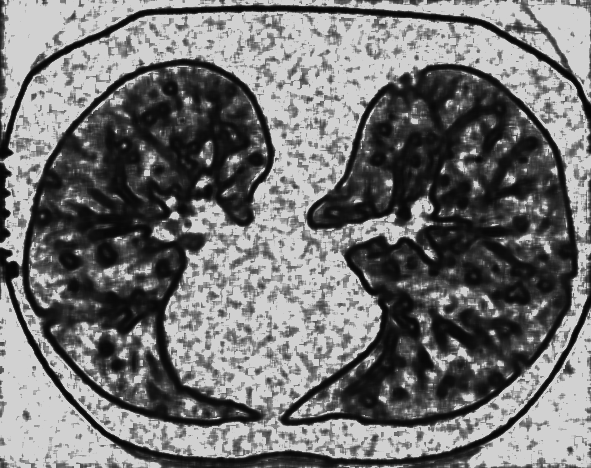

Example 2: restoration of images corrupted by blur and SPN or AWLN. In this example we evaluate the performance of the proposed TV-L1 model on three medical test images lungs (), Fig. 5 (a), ecography (), Fig. 6 (a), and aneurism (), Fig. 7 (a), synthetically corrupted by Gaussian blur of parameters band=5 and sigma=1 and by two types of impulsive noise, namely SPN and AWLN.

![]() |

| (a) original | (b) TV-L1 (ISNR = 11.04) | (c) zoom of (b) |

| (d) corrupted | (e) TVp-L1 (ISNR = 12.48) | (f) zoom of (e) |

| (g) -map () | (h) TV-L1 (ISNR = 15.30) | (i) zoom of (h) |

| (l) -map () | (m) TV-L1 (ISNR = 16.56) | (n) zoom of (m) |

First, for what concerns corruptions by SPN, in Figs. 5, 6, 7 we report for the three considered test images the original and corrupted image together with the estimated -maps in the first column (with the size of the neighborhoods used for the -maps estimation reported in the captions), the restoration results, obtained by the four compared methods, in the second column (with the achieved ISNR values in the captions) and a zoomed detail of the restored images - green- bordered in Figs. 5 (a), 6 (a), 7 (a) - in the last column.

The reported ISNR values as well as the visual inspection of the restored images and of the zoomed details strongly indicate how the proposed space-variant regularizer allows for higher quality restorations. In particular, it is worth remarking how, with respect to the space-variant TV model, the additional degrees of freedom represented by the scale parameters used in our proposal, yield a sufficient additional flexibility for avoiding unwanted spurious effects - see, e.g., spikes in Figs. 5 (i), 6 (i), 7 (i).